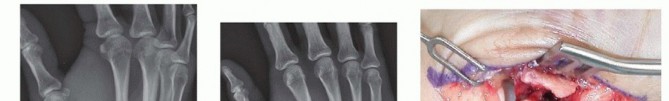

Open Reduction and Internal Fixation (ORIF) - Wagner Approach

For fractures with large volar-ulnar fragments (>20% of the articular surface), displaced Rolando fractures, or cases where closed reduction fails, ORIF is unequivocally mandated. The classic Wagner approach provides unparalleled exposure to the thumb CMC joint. A curvilinear incision is made along the glabrous border of the thenar eminence, curving dorsally at the level of the CMC joint.

Meticulous superficial dissection is required to identify and protect the sensory branches of the superficial radial nerve dorsally and the palmar cutaneous branch of the median nerve volarly. The thenar musculature (abductor pollicis brevis and opponens pollicis) is sharply elevated from the metacarpal shaft and retracted volarly. The joint capsule is then incised longitudinally or in an L-shaped fashion to expose the articular surface. The hematoma is evacuated, and the fracture fragments are meticulously debrided of interposed soft tissue.

For a large fragment Bennett fracture, the shaft is reduced to the volar-ulnar fragment using a pointed reduction clamp. Provisional fixation is achieved with a K-wire. A 1.5mm or 2.0mm lag screw is then placed perpendicular to the fracture plane. The near cortex must be overdrilled (gliding hole) and the far cortex underdrilled (thread hole) to achieve true interfragmentary compression. The screw head should be countersunk to prevent hardware prominence beneath the thenar muscles.